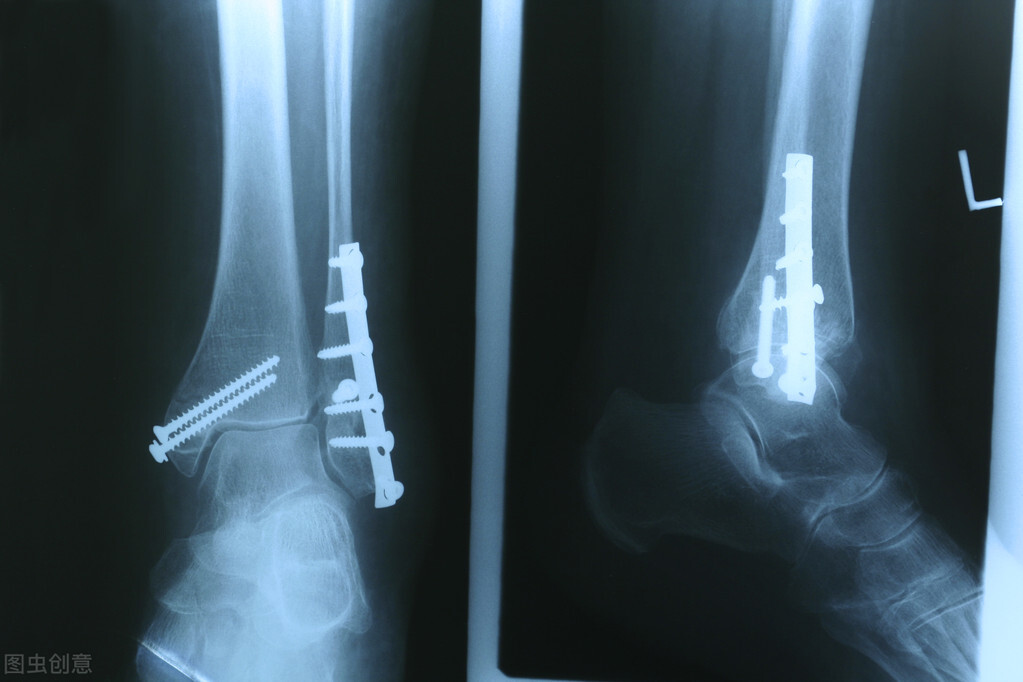

4、骨折

骨质疏松引起的骨折也被称为脆性骨折 , 骨量减少 , 骨密度下降 , 骨脆性增加 , 在日常的活动中 , 受到轻微